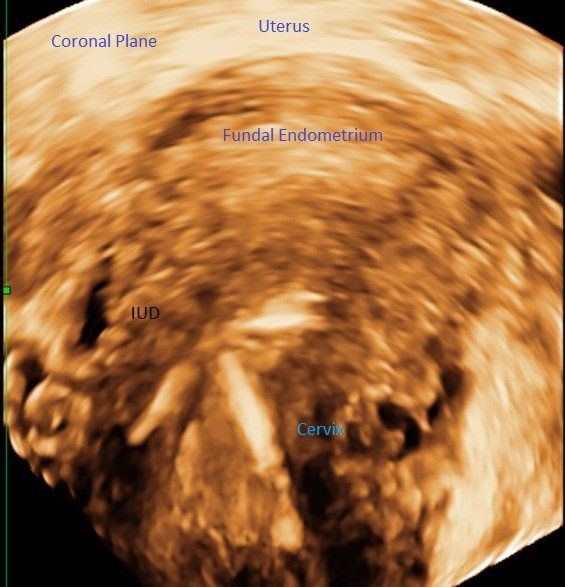

This case demonstrates the utility of 3D ultrasound, using the coronal plane as a reference point, for patients with an IUD who have pelvic pain.